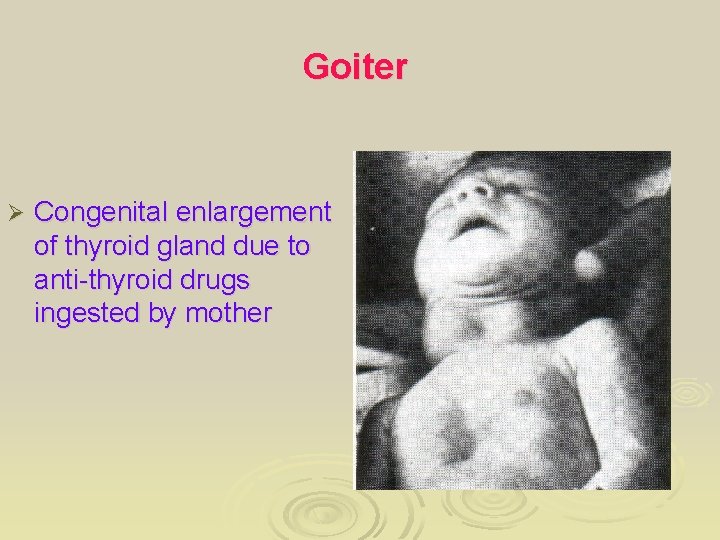

Goiter Ø Congenital enlargement of thyroid gland due to anti-thyroid drugs ingested by mother